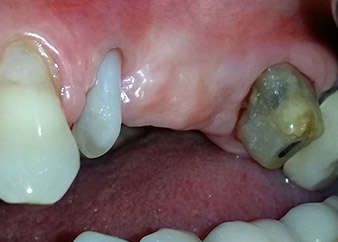

Междинен резултат след два месеца

Фигури 17 и 18 показват клиничния резултат два месеца след операцията. Зъб 24 показва намалена подвижност на Милър клас 1 и меките тъкани не са възпалени. Сондирането е избегнато на този етап, за да се избегне повторно възпаление и нарушение на епителната надстройка. Планиран е контролен преглед за повторно отваряне и поставяне на оздравителни абатмънти, шест месеца след поставяне на имплантите.

Два месеца след операцията, пациентката не чувства болка.

Фиг. 17: Два месеца след операцията, пациентката не чувства болка и зоната не е възпалена.

след операцията

Фиг. 18: Зъб 24 вече показва по-малко подвижност.